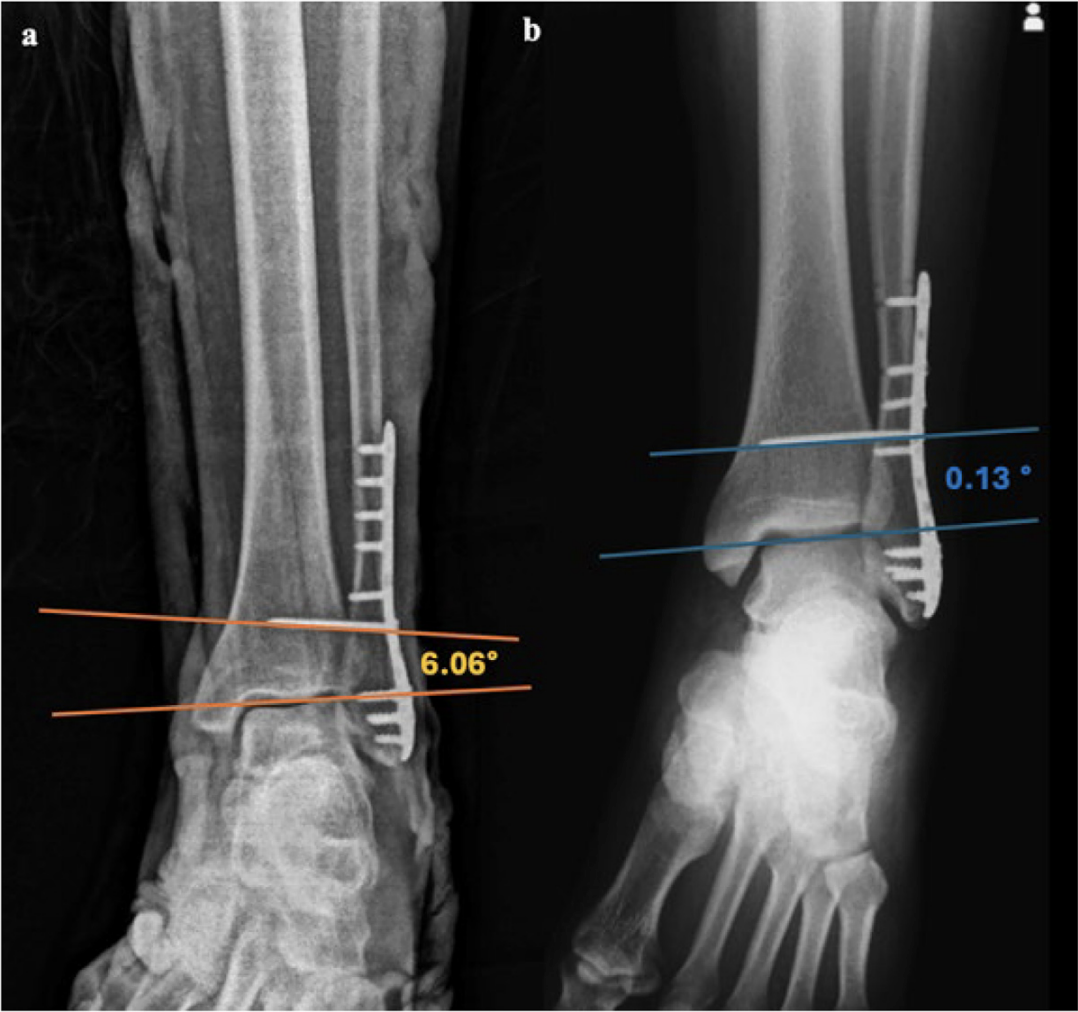

▲图示 a:下胫腓联合螺钉成角超出踝关节线±3°的患者术后X线片;b:下胫腓联合螺钉成角在踝关节线±3°范围内的患者术后X线片。

两组患者的分组依据为螺钉成角:

1组(平行组):螺钉成角在-3° 至+3°之间。包括首次置入即达到解剖学理想角度,以及多次尝试后才将螺钉调整至目标成角的病例。

2组(非平行组):螺钉成角超出上述范围。包括术中无意偏差、解剖结构限制导致的偏差,以及术中评估认为偏差可接受(为减少透视暴露及手术时长)而未予调整的病例。